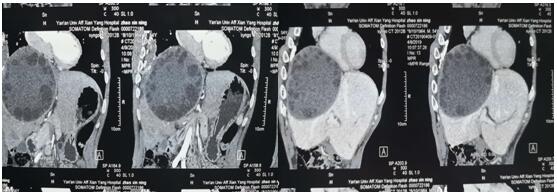

術前CT和三維重建